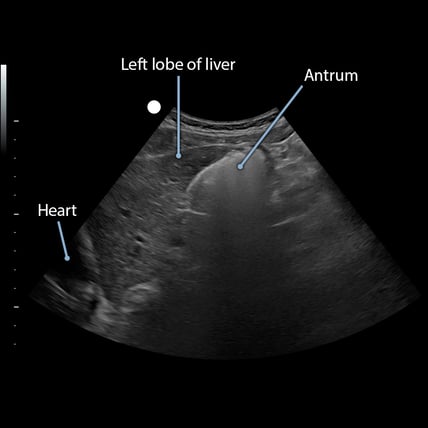

👩‍⚕️ Scanning & Imaging Tips: Gastric Frosted Glass Appearance RLD Position

dvr_20240508_1026_00_49_23_Solids-Sag-5min-001

When gastric ultrasound is performed shortly after the ingestion of solids, it often generates a 'frosted glass' appearance, which obscures the visualization of anatomic structures deep to the anterior wall of the stomach. Placing the patient in a right lateral decubitus position and repeating the exam 60 to 90 minutes later can significantly improve image quality. This improvement results from the combination of time allowing for gastric emptying and the migration of gas to non-gravity dependent regions of the stomach, which enhances sound wave transmission.